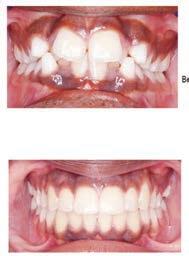

Christopher Chung, DMD

Smile Again Dental Group 818-776-9300

์์น์ง์ ๋ง์น๊ณ ๋์ ๊ฐ๊ธ ํ ๋ฒ ํ๋ฉด, ์

์์ด ํจ์ฌ ๊ฐ์ดํด์ง๊ณ ์์พํ ์ฃ . ์ฌ์ค ๊ฐ๊ธ์ ๊ทธ๋ฅ ์๋ฌด๊ฑฐ๋ ์จ๋ ๋ค ๋น์ทํ ๊ฒ ๊ฐ์ง๋ง, ์ฑ๋ถ๊ณผ ์ฉ๋

์ ๋ฐ๋ผ ๊ฝค ํฐ ์ฐจ์ด๊ฐ ์์ต๋๋ค. ์ด๋ค ๊ฐ๊ธ์ด ์น์ ๊ฑด๊ฐ์ ๋์์ด ๋๋ ์ง, ๋ ์ธ์ ์ด๋ป๊ฒ ์ฌ์ฉํ๋ ๊ฒ ์ข์์ง ์กฐ๊ธ ๋ ์์ธํ ์ ๋ฆฌํด๋ดค์ต๋ ๋ค.

๊ทธ๋ค์์ ํญ๊ท ์ฑ๋ถ์ด ๋ค์ด ์๋ ๊ฐ๊ธ์

๋๋ค. ๋ํ์ ์ผ๋ก ํด๋ก๋ฅดํฅ์

๋ ์ฑ๋ถ์ด ์๋๋ฐ, ์ด๋ ์๋ชธ ์งํ์ด๋ ์ฌํ ์ผ์ฆ์ด ์์ ๋ ํจ๊ณผ์ ์

๋

๋ค. ์

์ ์ธ๊ท ์ ํ์คํ๊ฒ ์ต์ ํด์ฃผ์ง๋ง, ๋จ์ ๋ ์์ด์. ์ค๋ ์ฐ๋ฉด ์น

์๊ฐ ๋๋ ๊ฒ ์ฐฉ์๋๊ฑฐ๋ ์์ ๋ง์ด ๋ค๋ฅด๊ฒ ๋๊ปด์ง ์ ์์ต๋๋ค. ๊ทธ๋์

์ด๊ฑด ๋ณดํต ์น๊ณผ์์ ์ค์ผ์ผ๋ง์ด๋ ์๋ชธ ์น๋ฃ ํ์ ๋จ๊ธฐ๊ฐ ์ฒ๋ฐฉํ๋ ๊ฒฝ

์ฐ๊ฐ ๋ง์ต๋๋ค. ๋งค์ผ ์ฐ๋ ๋ฐ์ผ๋ฆฌ ๊ฐ๊ธ ์ด๋ผ๊ธฐ๋ณด๋ค๋ ์น๋ฃ์ฉ์ผ๋ก ์๊ฐ ํ์๋ฉด ๋ ๋ง์ต๋๋ค.

๋ฌด์์ฝ์ฌ

์

์์ด ์๋ฏผํ๊ฑฐ๋ ์๊ทน์ ์ฝํ ๋ถ๋ค์ ๋ฌด์์ฝ์ฌ ๊ฐ๊ธ์ ๋ง์ด ์ฐพ์ต๋ ๋ค. ์์ฝ์ฌ์ด ๋ค์ด ์์ผ๋ฉด ๊ฐ๊ธํ ๋ ํ๋๊ฑฐ๋ฆฌ๊ณ ๋ฐ๊ฐ์ด ๋๋์ด ์๋๋ฐ, ๋ฌด์์ฝ์ฌ ์ ํ์ ํจ์ฌ ์ํด์ ์์ด๋ค์ด๋ ์ ๋ง์ด ๋ฏผ๊ฐํ ๋ถ๋ค์๊ฒ ์ ํฉํฉ๋๋ค. ์์ฆ์ ๋ฌด์์ฝ์ฌ ๊ฐ๊ธ ์ค์์๋ ๊ตฌ์ทจ ์ ๊ฑฐ๋ฅผ ๊ฐ์กฐํ ์ ํ์ด ๋ง์์, ์

๋์๊ฐ ์ ๊ฒฝ ์ฐ์ผ ๋ ๋์์ด ๋๊ธฐ๋ ํฉ๋๋ค.

๊ทธ๋ฆฌ๊ณ ์์ฆ์ ๋ฏธ๋ฐฑ ํจ๊ณผ๋ฅผ ๊ฐ์กฐํ๋ ๊ฐ๊ธ๋ ๋์ ๋์ฃ . ์ปคํผ๋ ์ฐจ๋ฅผ ๋ง

์ด ๋์๋ ๋ถ๋ค์ด ๊ด์ฌ์ ๊ฐ๋๋ฐ, ์ฌ์ค ์ด๊ฑด ์น์ ๋ณธ์ฐ์ ์์ ๋ฐ๊พธ๋ ๊ฑด ์๋๊ณ , ํ๋ฉด์ ๋ถ์ ์ฐฉ์์ ์ด๋ ์ ๋ ์ค์ฌ์ฃผ๋ ์ ๋๋ผ๊ณ ๋ณด์๋ฉด ๋ฉ ๋๋ค. ์น์ ๋ฏธ๋ฐฑ ์น๋ฃ์ฒ๋ผ ํ ๋๋ผ๋งํฑํ ํจ๊ณผ๋ ์์ง๋ง, ์ํ ์ต๊ด๊ณผ ํจ๊ป ์ฐ๋ฉด ์กฐ๊ธ์ ๋ฐ์์ง ๋๋์ ๋ฐ์ ์ ์์ด์.